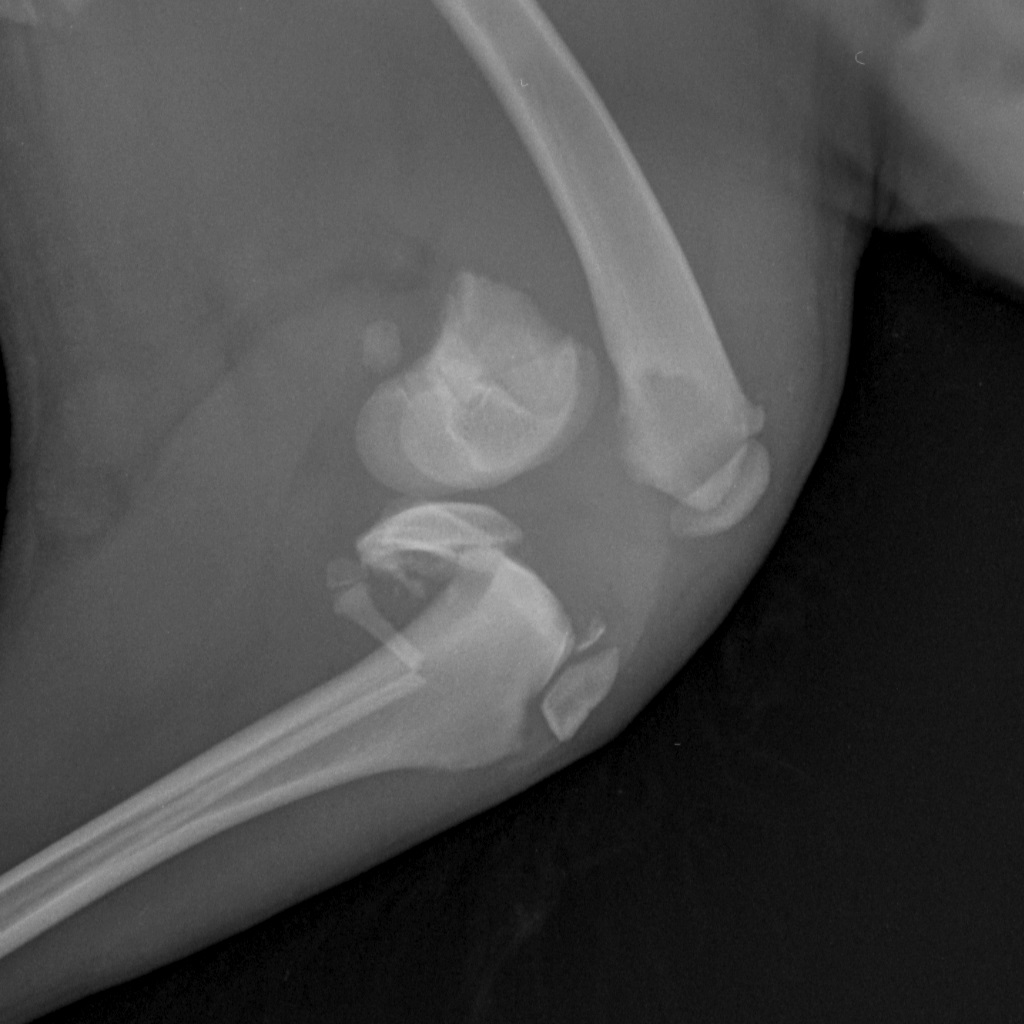

Вот такая бяка у девочки((

Такой мерзкий перелом бывает при прямом ударе по колену

Жуть какой перелом! Далекому от медицины человеку - и то смотреть страшно. Впрочем, неудивительно если её из машины на ходу выкинули.

А подсобрать получше эти обломки невозможно, слишком тоненькие косточки?